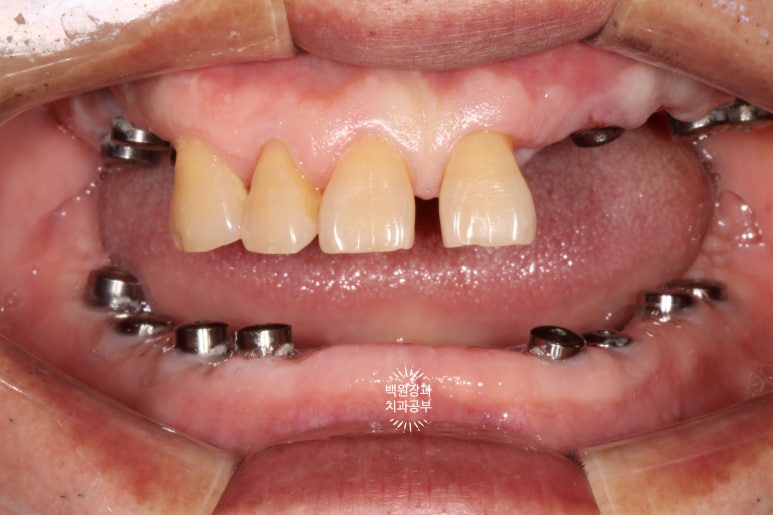

위아래 임플란트에 모두 치유지대주를 연결시켜드렸습니다.

조금 사이보그 (?!) 같긴 하지만.. 이제 어느 정도 치료의 끝이 보이네요~!

임플란트에 기둥을 연결하고, 임시치아를 붙여 저작 연습을 해봅니다!

임플란트들이 내 잇몸뼈와 잘 결합이 된다면, 이제 슬슬 밥먹는 연습을 해보실 시간입니다.

기존에 있었던 모든 임플란트에 맞춤형 지대주 (custom abutment)를 연결해드리고,

상부에 임시치아를 붙여드리게 됩니다.

임시치아를 붙여드린 뒤 사진입니다.

네개만 남은 앞니도 임시치아로 함께 제작해 드렸어요.

1달 정도 사용 하신 뒤 찍은 사진이라 색상이 조금 좋진 않지만.... 최종보철물은 다를겁니다.!!!